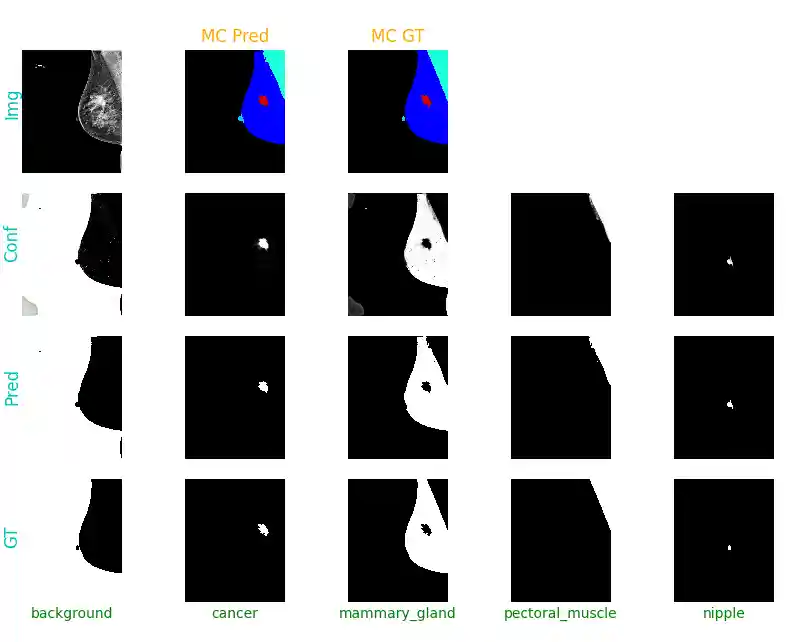

I've trained a ResU-Net++ model, inputting images of 1024x1024 (preserved aspect ratio, vertical axis as reference). The model is trained to perform multi-class semantic segmentation of cancer, mammary gland, pectoral muscle and nipple:

| metrics | cancer | mammary gland | pectoral muscle | nipple | overall |

|---|---|---|---|---|---|

| DSC | 0.279 | 0.976 | 0.946 | 0.474 | 0.669 |

| IOU | 0.220 | 0.955 | 0.920 | 0.373 | 0.617 |

Due to the downsampling of images, too much information is lost to produce satisfactory tumour segmentation (in terms on DSC/IOU). Improvements can be made by working patch-wise, working with full or higher resolution, but it might degrade performance on other classes, so it depends on the use case.